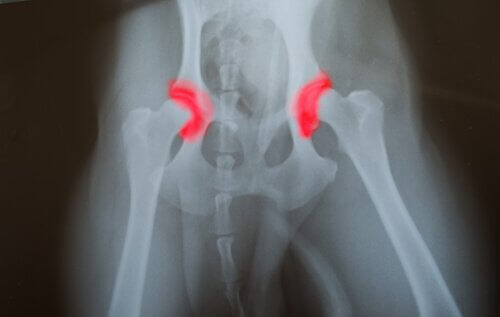

Om valpen har fått för mycket mat så kommer han gå upp i vikt och växa snabbare än han bör. Detta kommer anstränga hans skelett alltför mycket och kan orsaka följande sjukdomar:

- Osteokondros

- Höftdysplasi

- Problem med koronoidprocessen

1974 analyserade en studie 12 par grand danois som hade en kost med höga nivåer av protein, fosfor och kalorier. De sjukdomar vi tog upp ovan var mer förekommande hos hundar som åt denna typ av kost.

Jämfört med stora hundar som hade en obalanserad kost så hade de med en balanserad konst mindre hälsoproblem relaterade till överväxt. Höftdysplasi var en av de mest förekommande sjukdomarna hos äldre hundar som hade fått för mycket mat.

Hos vuxna hundar kunde övermatningen orsaka ett antal hälsoproblem. Nedbrytning av leder verkade vara ett av de mest vanliga symptomen hos äldre hundar.